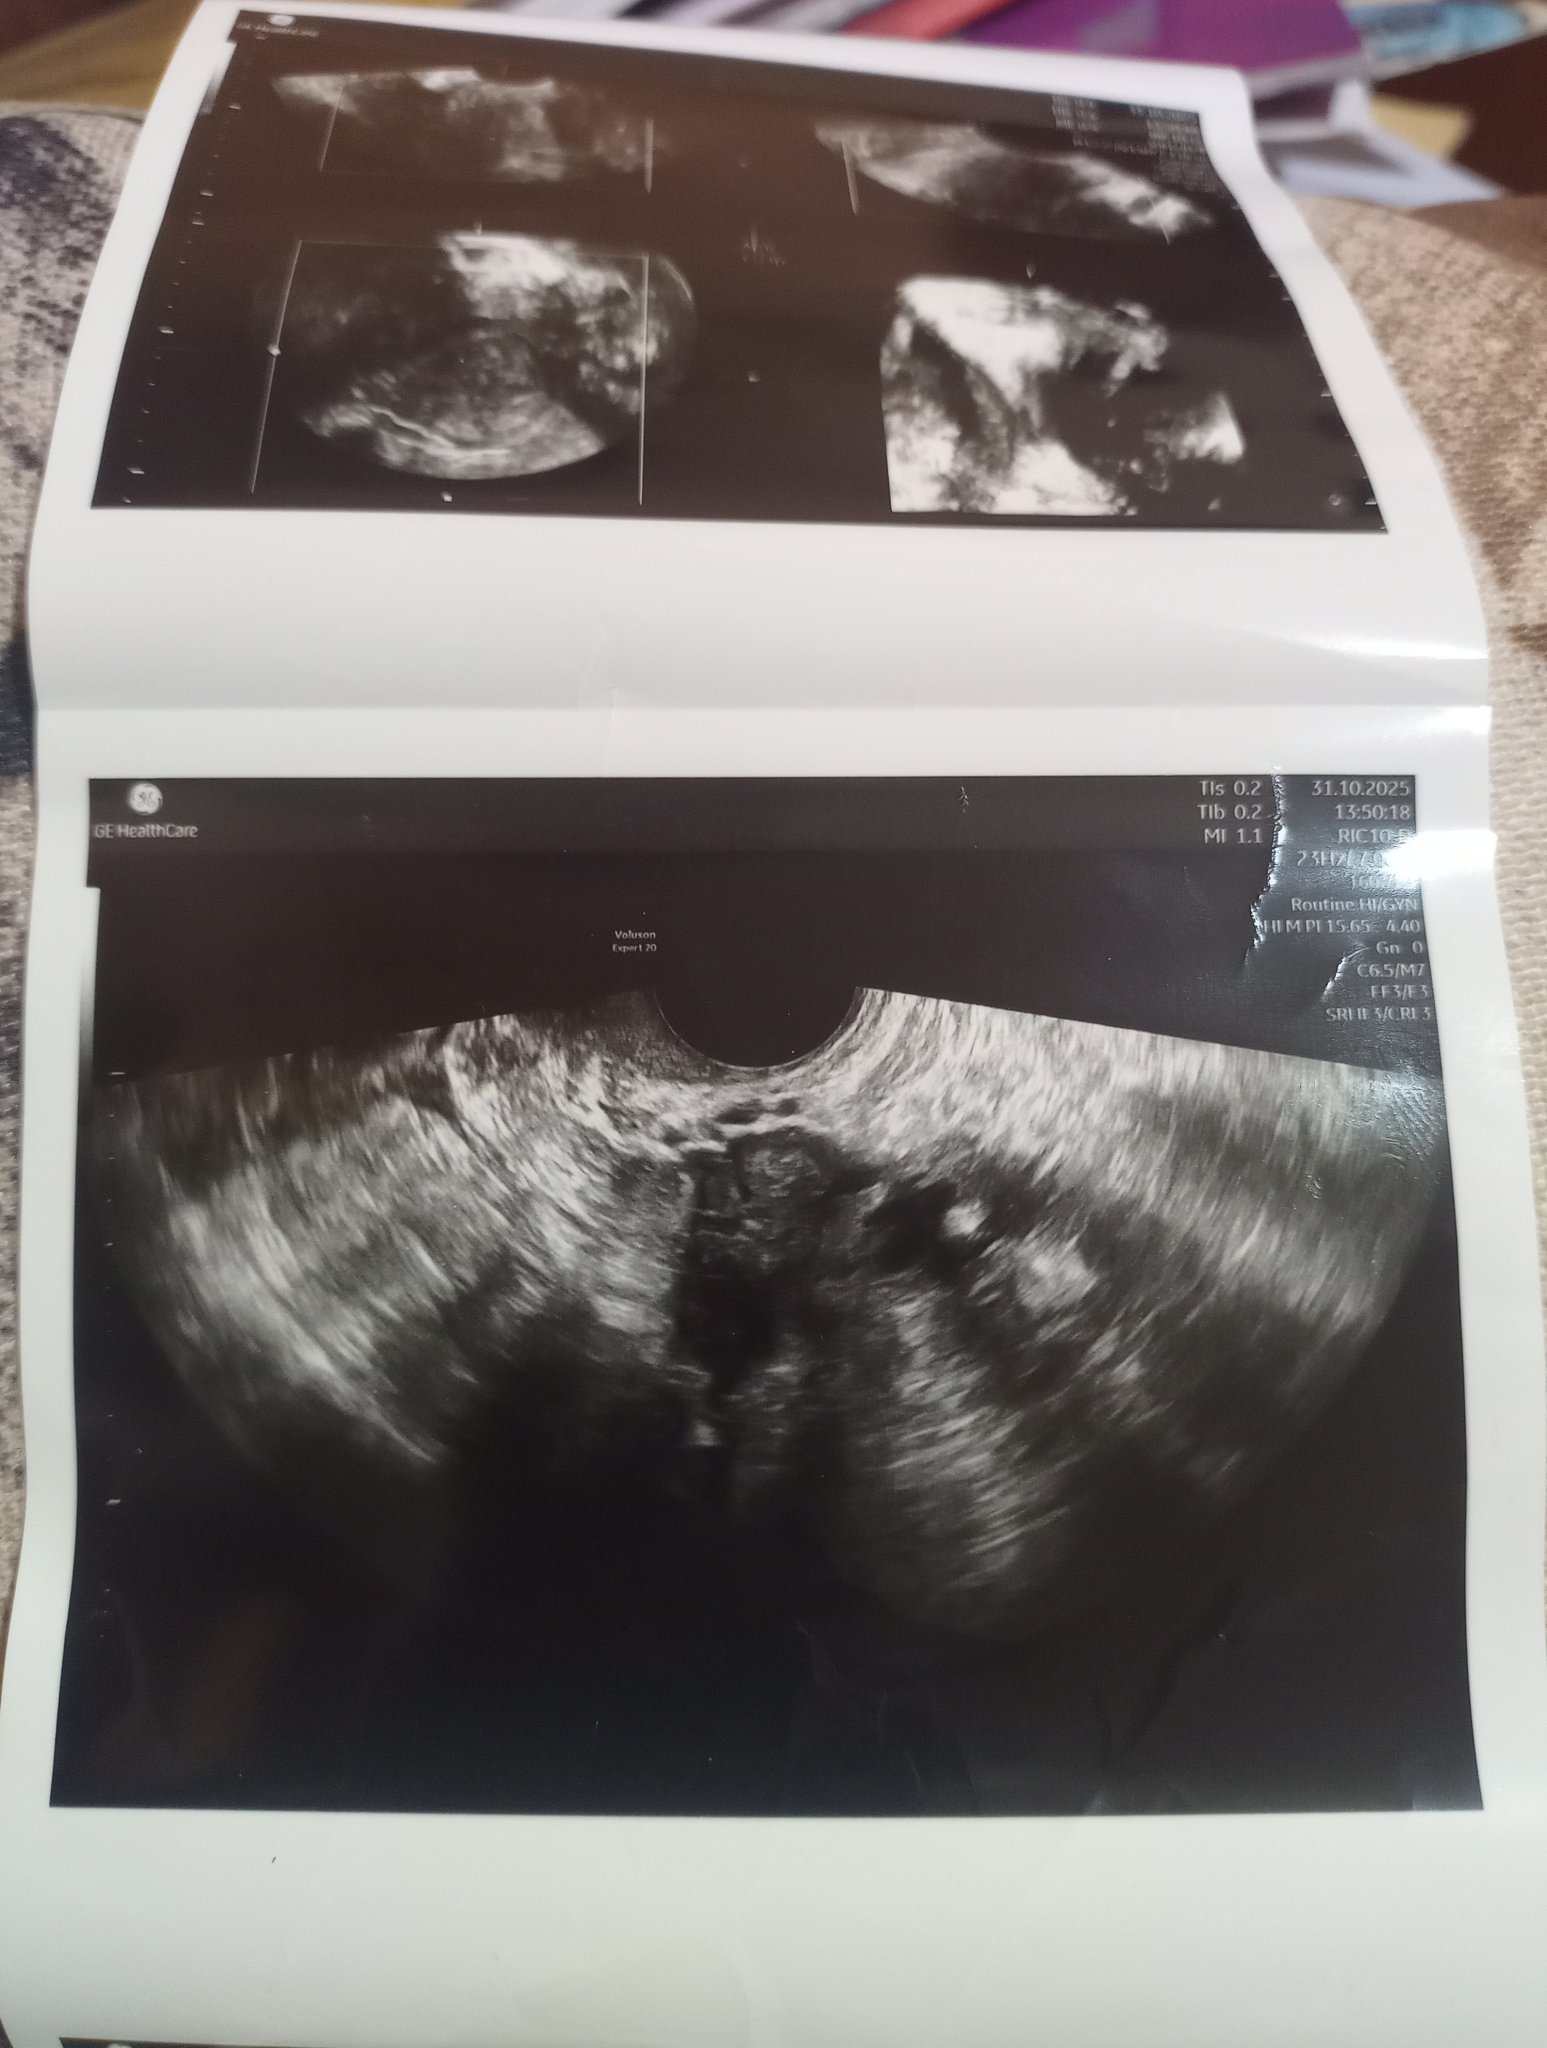

Какво представляват белите точки в плодния сак на ехографската снимка?

Какво представлява жълтото тяло на ехографската снимка?

Какво представляват черните точки в матката на ехографската снимка?